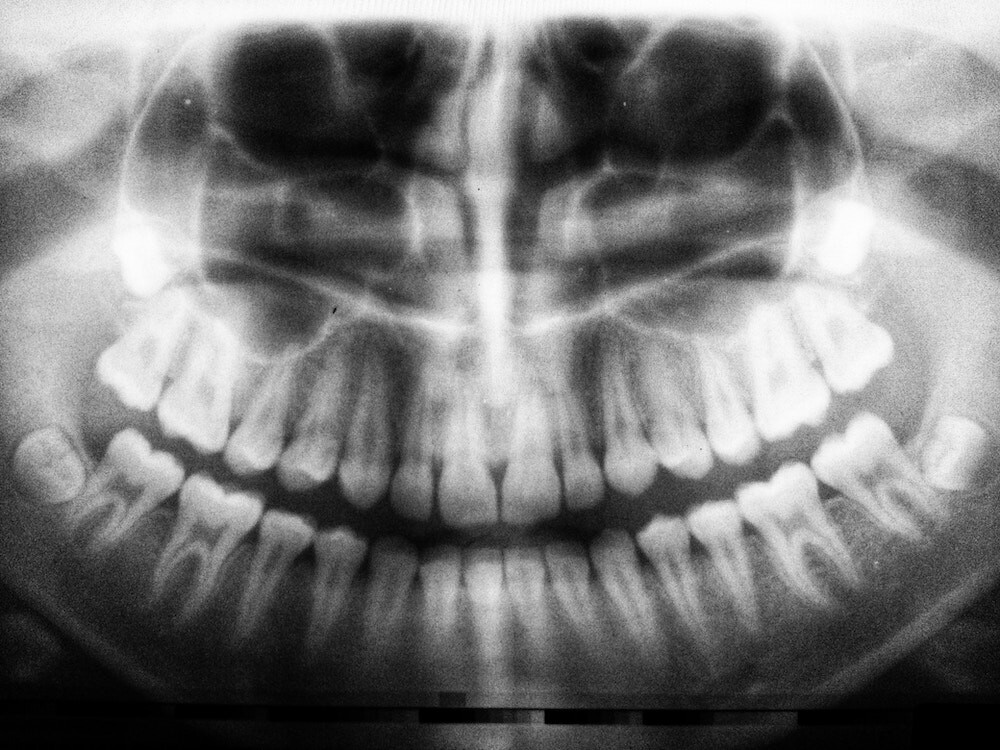

Bone Resorption: Why It Happens And What To Do Next

Our bodies are an excellent example of “use it or lose it.” We’re made up of billions of living cells in a state of constant change. If we fail to exercise or move around, our bodies divert those valuable resources elsewhere.

As a result, our muscles start to shrink — and the same concept applies to our bones.

WHAT IS BONE RESORPTION?

Bone resorption is the biological process in which our bodies break down our bone tissue and release the minerals into our bloodstream. It’s a natural function that allows our bones to heal and renew themselves over time.

It’s a cycle of breaking down and regenerating — but the process can be interrupted when your body believes it no longer needs bone mass in that particular area. As a result, the bone gets broken down but not replaced.

One of the most common places for resorption to occur is in the jawbone.

WHAT CAUSES JAWBONE RESORPTION?

One of the main reasons for jawbone resorption is the loss of teeth.

When the root is removed, your jawbone no longer receives the stimulus and pressure of chewing. This causes your body to believe that it no longer requires the same bone density in that area.

When a tooth is extracted or lost, up to 25% of bone density can be lost in the first year — and the process continues. Jawbone loss causes your face to shrink, which may make you appear older than you actually are.

However, if you’re a current or future denture user, there are a few steps you can take to reduce the rate of resorption.

HOW TO SLOW JAWBONE RESORPTION AS A DENTURE USER

If you’re concerned about jxawbone resorption, you may want to consider dental implants over traditional dentures. Dental implants replace the root and crown of some of your natural teeth — which can stimulate your jawbone to create bone mass.

Although it isn’t perfect, this little bit of pressure and stimulus can slow the resorption process significantly — which means fewer visits to your denturist for adjustments and refittings.

It’s also important that you remove your dentures overnight. Not only will this give you an opportunity to properly clean and soak your dentures but leaving them in for long periods of time can actually speed up the resorption process.

The constant pressure can cause your jaw to become inflamed — which can cause the rate of resorption to increase significantly.